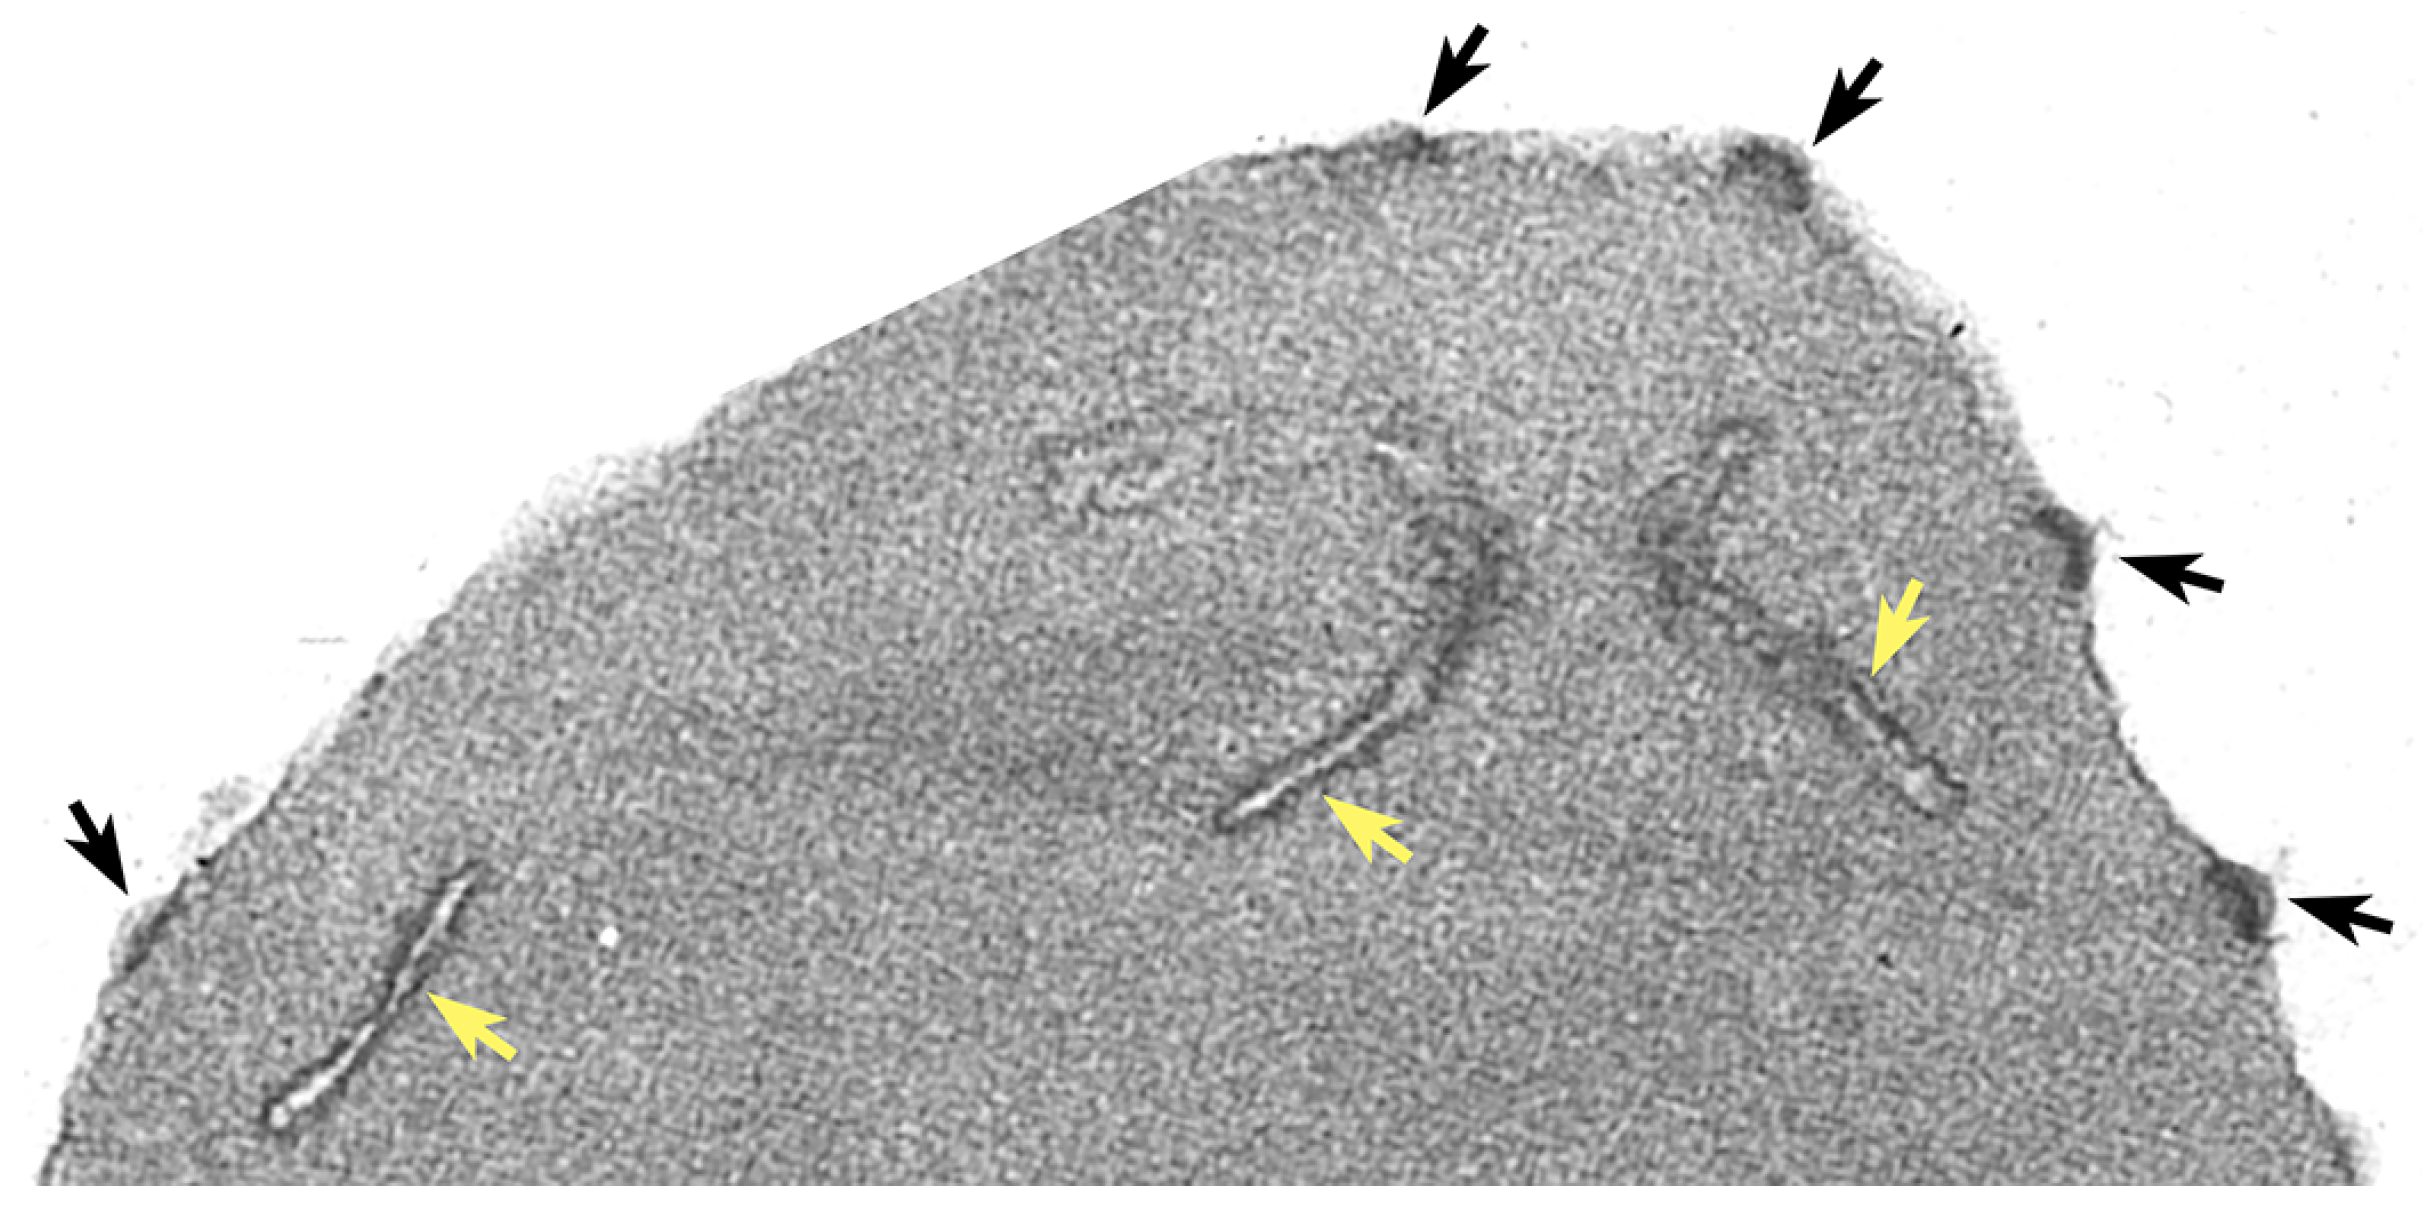

Figure 1.

Ultrastructure of knobs and Maurer’s clefts. An electron micrograph of an infected erythrocyte showing knobs (black arrows) and Maurer’s clefts (yellow arrows). Electron micrograph provided by H. Norbert Lanners.

Another important factor associated with P. falciparum virulence is the sequestration of infected erythrocytes in the deep tissues. This sequestration of infected erythrocytes is due to the cytoadherence of infected erythrocytes to endothelial cells of the capillaries, thereby decreasing blood perfusion, and causing localized inflammation. Cytoadherence is mediated by electron-dense protuberances on the surface of infected erythrocytes called knobs (Figure 1). These knobs were described in the early days of ultrastructural research on the malaria parasite [3], and the importance of knobs in the pathophysiology of severe falciparum malaria has been known for decades [4,5].

Knobs are electron-dense protuberances on the surface of P. falciparum-infected erythrocytes (see Figure 1). The electron-dense material making up the knob forms a cup-like structure 40–145 nm in diameter and approximately 50 nm in height [9]. It was recognized quite early that a parasite protein was correlated with knobs [10]. Sequencing of the gene for this knob-associated protein revealed three domains of repetitive sequence that are rich in lysine or histidine [11]. This knob-associated histidine-rich protein (KAHRP) is a major component of the knobs and is localized to the cytoplasmic face of the erythrocyte membrane (Figure 2). In addition, a spiral filament of unknown protein composition is also observed within the cup of the knob and forms a scaffold that binds KAHRP [9,12]. It is estimated that 60 KAHRP molecules make up a single knob [13] and KAHRP is likely the electron dense material of the knob.

Another membranous structure found in the host cytoplasm of P. falciparum-infected erythrocytes are the Maurer’s clefts [43]. The Maurer’s clefts are derived from the PVM and exhibit a flattened disk shape that is electron dense (see Figure 1). In addition, several parasite proteins that may play a role in the formation of the Maurer’s clefts or that may be residents of the Maurer’s clefts have been described (Table 1). Initially the Maurer’s clefts are mobile, and as the parasite matures, the clefts migrate to the erythrocyte periphery and become tethered to the cytoplasmic face of the erythrocyte membrane [44,45]. It is widely believed that Maurer’s clefts play a role in the movement of parasite proteins, especially PfEMP1, through the host erythrocyte cytoplasm to the erythrocyte membrane [46].